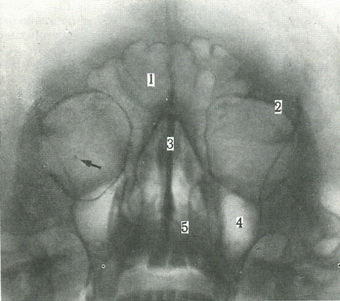

68. Оглядовий знімок очниць (за Л.Д. Линденбратену).

1 - лобова воздухоносная пазуха; 2 - кран очниці; 3 - перегородка порожнини носа; 4 - воздухоносная пазуха верхньої щелепи; 5 - нижня носова раковина.

На знімку в передній проекції зазвичай на тіні очниць нашаровуються тіні пірамід скроневих кісток. Щоб картина була більш зрозумілою, виконують підборіддя-носової знімок у передній проекції (рис. 68). На такому знімку визначають структуру кісткового краю входу в очну ямку, стан стінок і щілин очниці. Нижче очниць видно повітроносні пазухи, мають чіткі стінки.